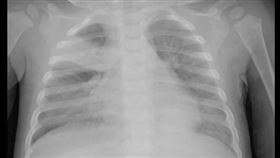

感冒症狀別輕忽!RSV肺炎風險比流感高3倍

RSV「呼吸道融合病毒」,雖然症狀跟流感相似,不過傳...

傳播力超強!出生21天女嬰感染RSV險重症

台中一名出生21天的新生女嬰出現嚴重咳嗽嘔吐、鼻塞、...

嬰幼兒感冒突喘得厲害 1病毒恐併發肺炎

「寶寶才感冒兩天,怎麼突然喘得厲害又不喝奶?」這樣的...

小孩咳不停恐RSV!醫:3大場域最容易群聚

最近適逢季節交替、氣溫變化大,是孩童呼吸道疾病的好發...

感染呼吸道「三大魔王」 男嬰肺炎插管

日前冷氣團一波波接力報到,嬰幼兒呼吸道感染案例快速增...